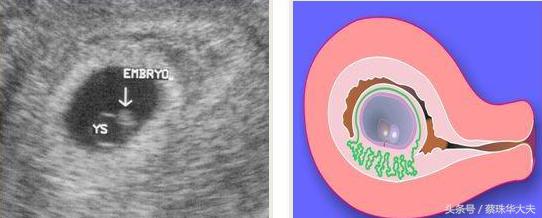

阴道超声准确率比腹部超声高,可以更早的鉴别怀孕是正常还是异常,是宫内怀孕还是宫外孕。

阴道B超探头放在阴道内,只要经过宫颈组织就直接看到在宫腔内的胚胎,哪怕只有很微弱的胎心或是很小的胚芽,都逃不过火眼金睛的小神探 阴道探头。